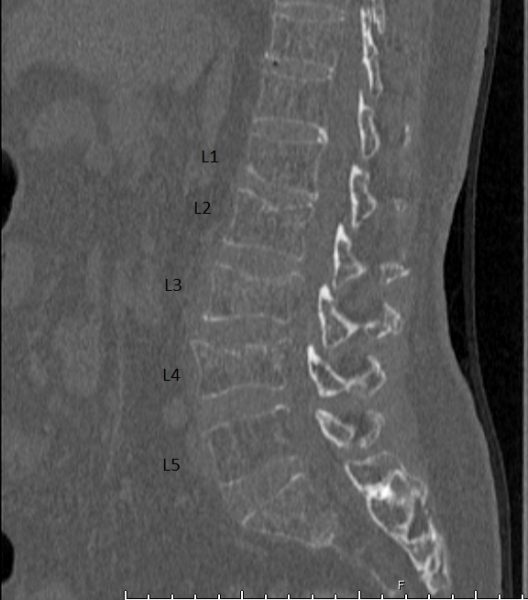

我给阿贵嫂做体检时,她的上肢没有大碍,下肢则虚弱无力,反射也偏低。起初我怀疑是马尾症候群,马上安排她做3D立体CT断层扫描,结果发现不是马尾症候群,而是因为第二至第四节腰椎(L2~L4)有崩塌的迹象,压迫神经根,造成疼痛。

磁力共振扫描显示,阿贵嫂的腰椎崩塌确有恶化趋向,主要神经管也受到压迫。我决定为她进行微创水泥椎体成形手术(Cement vertebroplasty),在X光透视引导下,将骨水泥注入崩塌的第3节腰椎,支撑受损的椎体,同时也做了椎板切除手术,舒缓受压的神经线。

崩塌惡化,主要神經管也受到壓迫。-499x600.jpg)